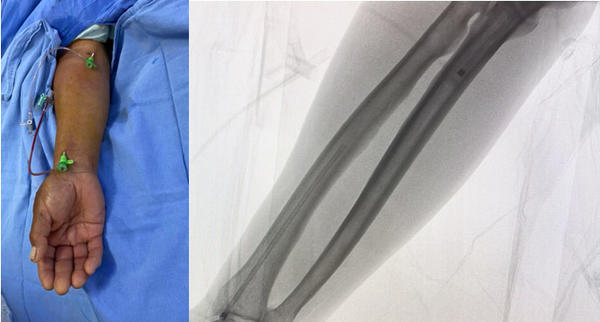

A venous and arterial access through right forearm was performed using basilic vein and proximal radial artery. A 6 French introducer sheath was placed (Figure 1).

Figure 1.